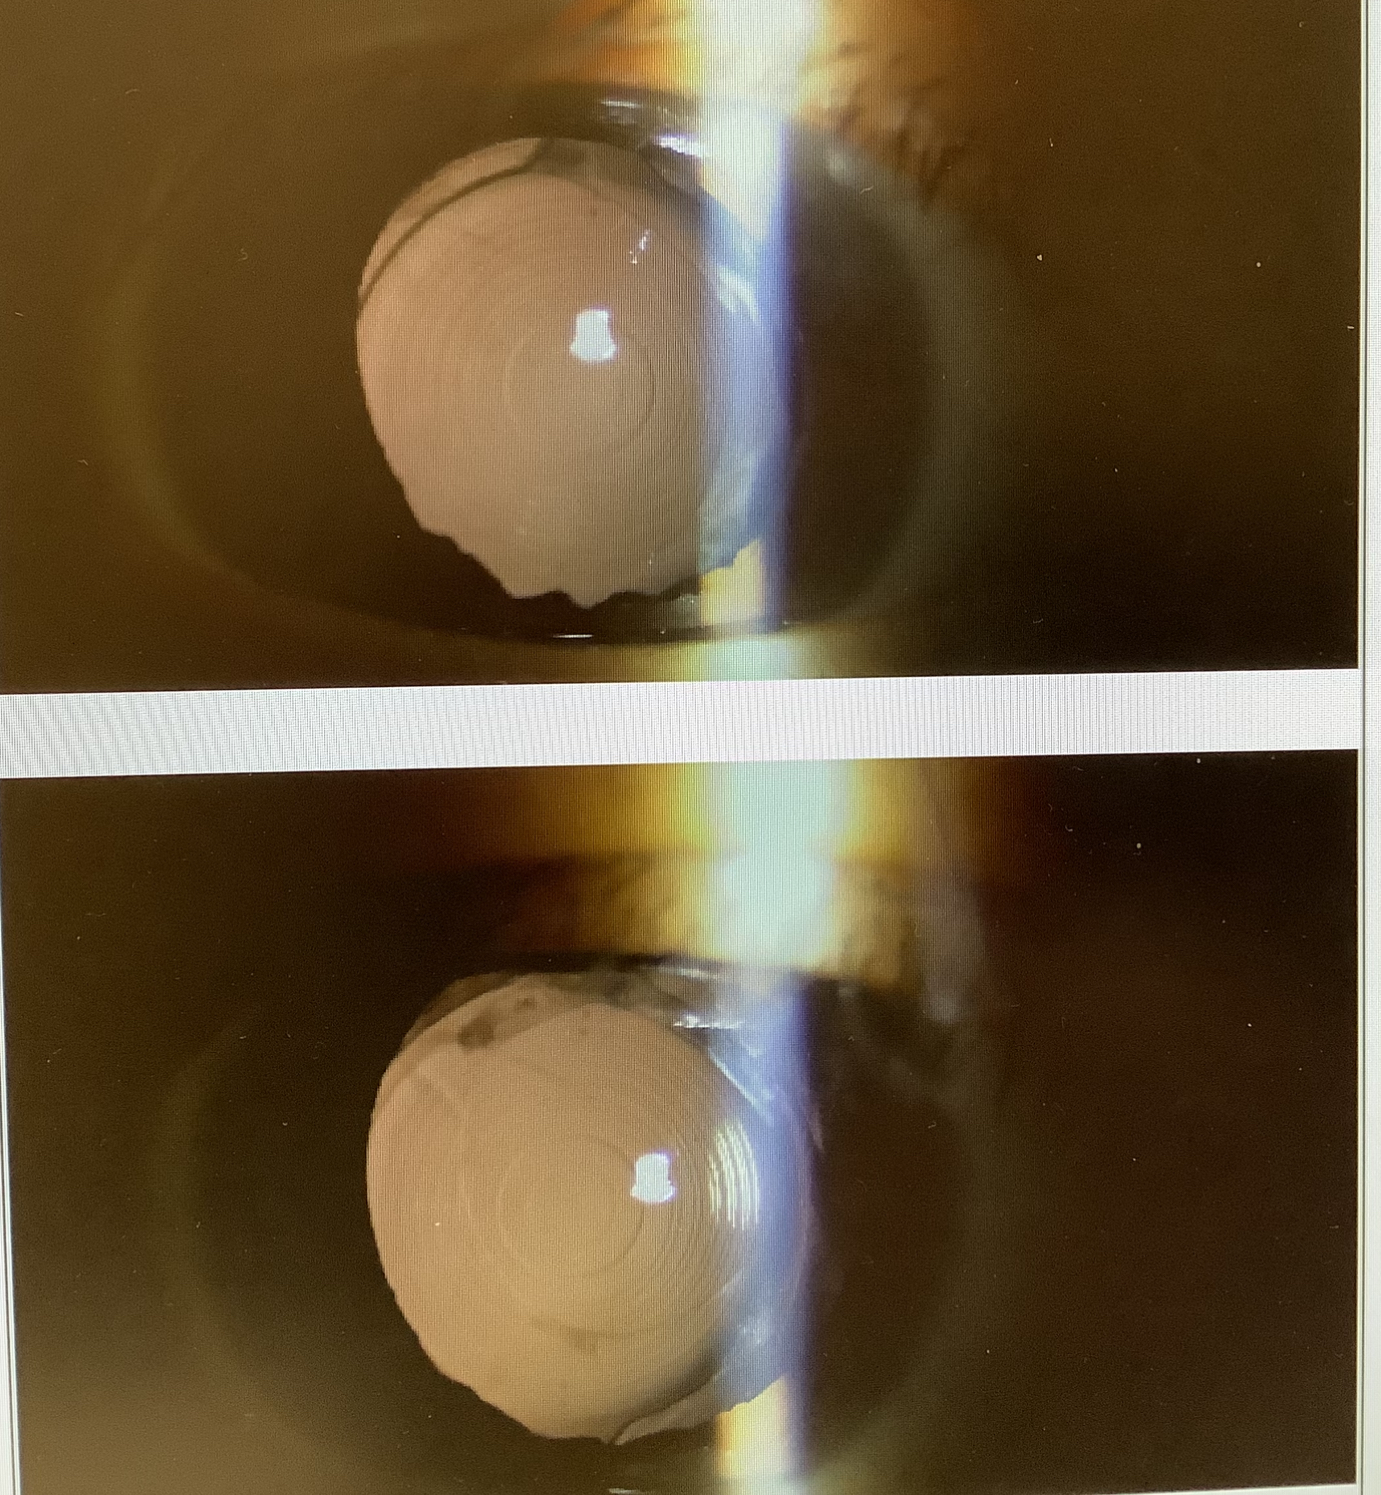

↑上が術後、したが術前。ちょっとわ分かりにくいですが、中心の位置が改善しています。